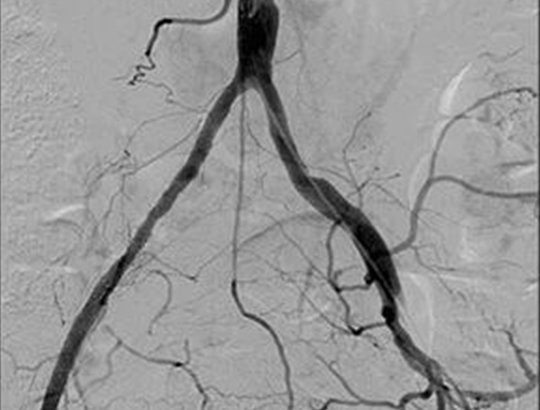

Advanced DSA functionalities

Features include Subtraction, Road Mapping, injector-linked acquisition, and precise stenosis measurement and calibration.